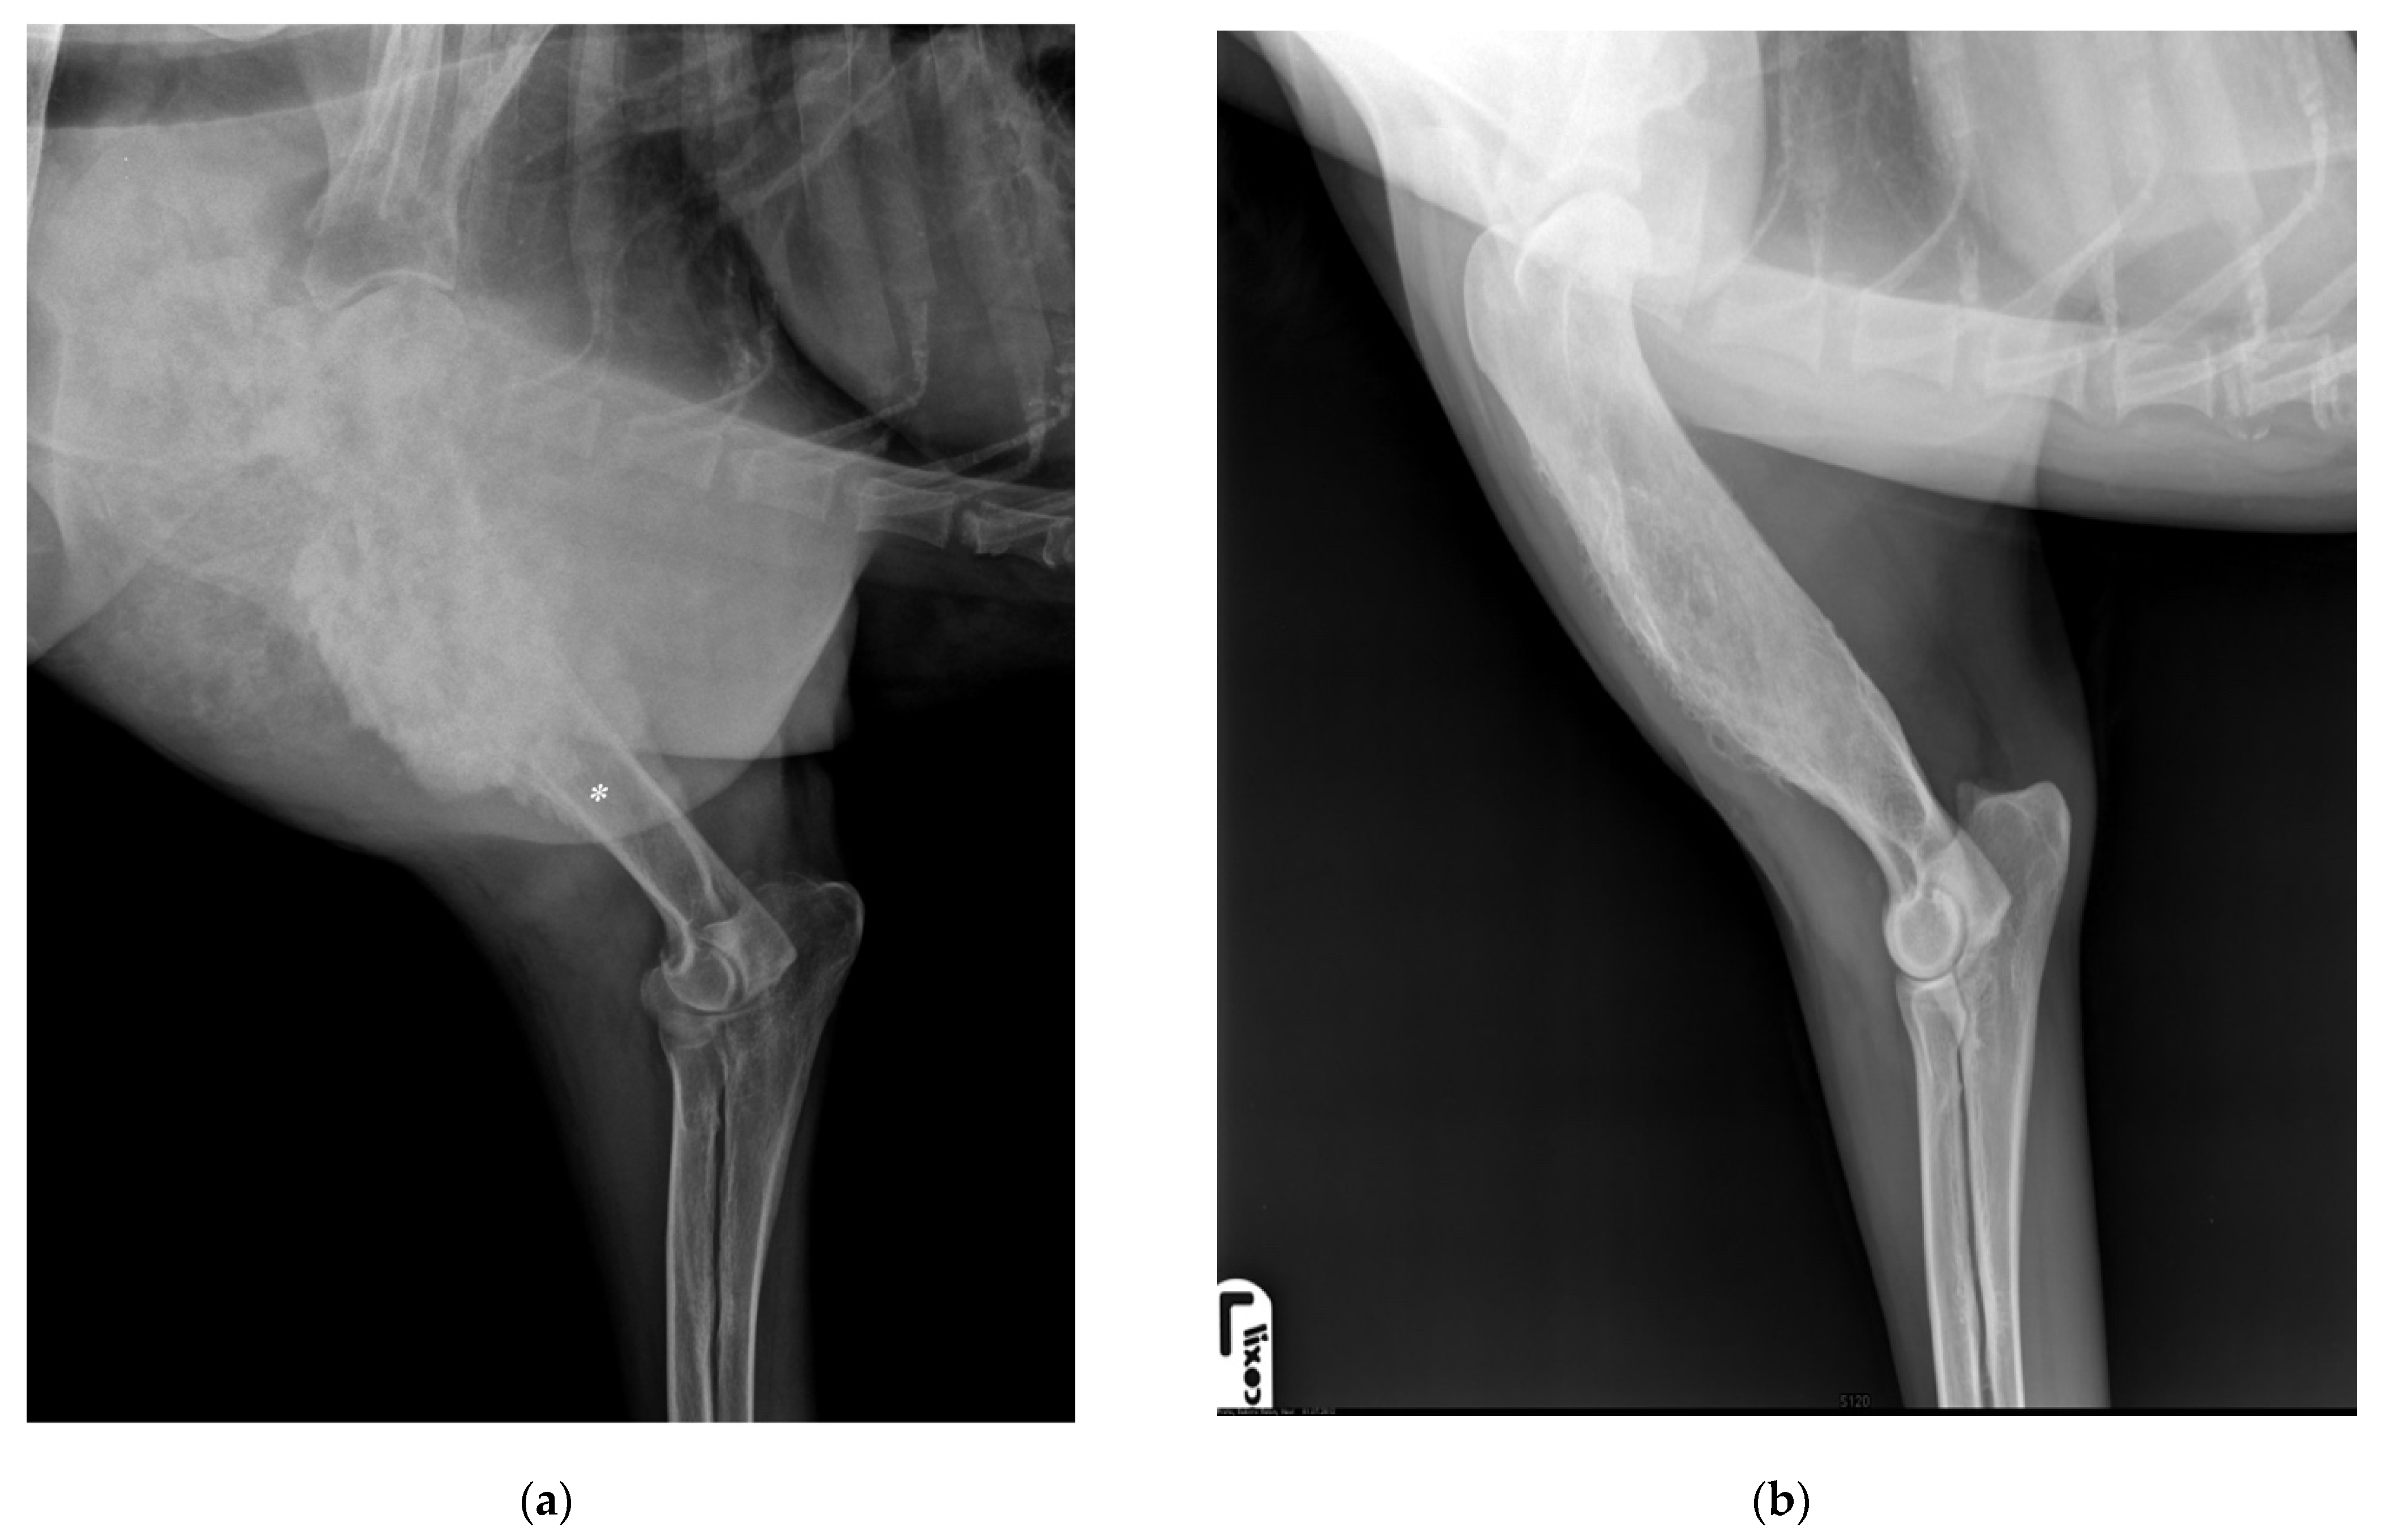

Aseptic necrosis of bone exhibiting a dense, uniform appearance with What Is Aseptic Necrosis In Dogs an aseptic necrosis of the femoral head of small breed juvenile dogs, particularly terriers, poodles, and miniature pinschers. aseptic femoral head necrosis in dogs. What are aseptic femoral head. aseptic necrosis, a deterioration of the femoral head seen in young miniature and small breeds of dogs, is associated with ischemia and avascular. Also frequently called avascular necrosis. What Is Aseptic Necrosis In Dogs.

[PDF] Radioulnar Ischaemic Necrosis in a Dog with Concurrent What Is Aseptic Necrosis In Dogs an aseptic necrosis of the femoral head of small breed juvenile dogs, particularly terriers, poodles, and miniature pinschers. aseptic femoral head necrosis in dogs. What are aseptic femoral head. Also frequently called avascular necrosis of the. legg calvé perthes disease (lcpd) is a developmental abnormality that usually affects young small breed dogs. aseptic necrosis, a deterioration. What Is Aseptic Necrosis In Dogs.